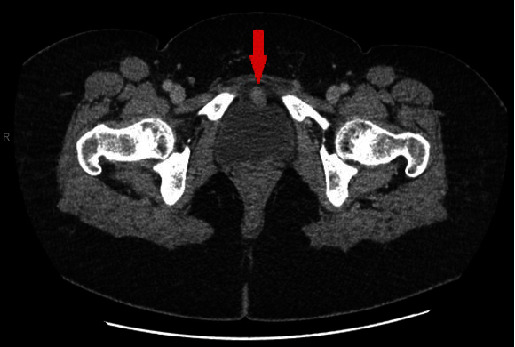

软骨瘤通常发生在骨骼中,在软组织中发现的文献有限。迄今为止,仅有 8 例膀胱软骨瘤的报道,且均为女性。在此,我们描述了一名 54 岁女性的病例,她的膀胱前壁长了一个软骨瘤。在进行造影剂增强计算机断层扫描(CT)时,意外发现右侧膀胱壁上有一个 5 毫米的增强病灶。随后的膀胱镜检查未发现任何异常,尿液分析和尿液细胞学检查也无异常。然而,CT 尿路造影再次证实了恶性肿瘤的怀疑,膀胱镜检查也验证了这一点。患者接受了经尿道膀胱肿瘤切除术,该肿瘤被确认为膀胱软骨瘤。在手术切口中,发现了粘膜下病变,组织病理学评估进一步证实了这一点。经过一年的影像学和尿液细胞学随访,未发现复发。该病例证实了之前的研究结果,并强调该病好发于五至七十岁的女性,预后良好。

Chondroma, commonly observed in the bones, has limited documentation when found in soft tissues. To date, only 8 chondromas in the urinary bladder have been reported, all in females. Here, we describe a 54-year-old female who presented with a chondroma located at the anterior wall of the urinary bladder. An incidental 5 mm enhanced focus was identified on the right bladder wall during a contrast-enhanced computerized tomography (CT). Subsequent cystoscopy did not reveal any abnormalities, and both urinalysis and urine cytology were unremarkable. However, a CT urogram reconfirmed suspicions of malignancy, which a cystoscopy validated. The patient underwent a transurethral resection of the bladder tumor, which was identified as a bladder chondroma. During the surgical incision, a submucosal lesion was found, which was further confirmed with histopathological evaluation. Over a year-long follow-up using imaging and urine cytology, no recurrence was observed. This case reinforces earlier findings and underscores the predilection for females between their 5th and 7th decades with a positive prognosis.